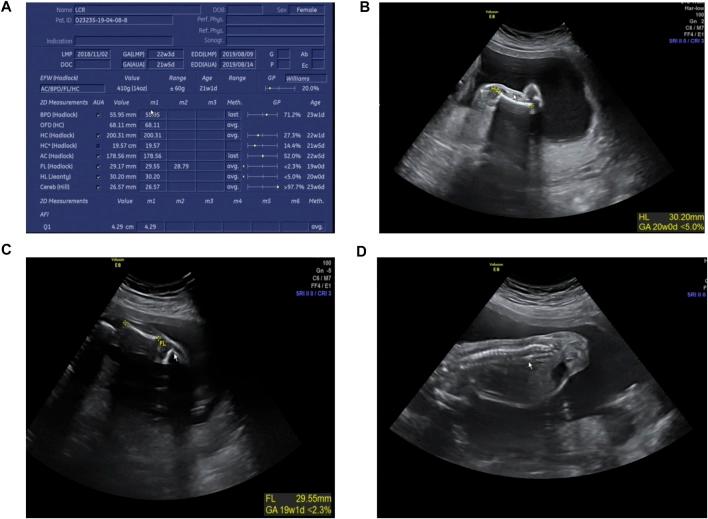

Spondyloepiphyseal dysplasia congenital (SEDC) is a rare chondrodysplasia caused by dominant pathogenic variants in . Here, we detected a novel variant c.3392G > T (NM_001844.4) of in a Chinese family with SEDC by targeted next-generation sequencing. To confirm the pathogenicity of the variant, we generated an appropriate minigene construct based on HeLa and HEK293T cell lines. Splicing assay indicated that the mutated minigene led to aberrant splicing of pre-mRNA and produced an alternatively spliced transcript with a skipping of partial exon 48, which generated a predicted in-frame deletion of 15 amino acids (p. Gly1131_Pro1145del) in the COL2A1 protein. Due to the pathogenicity of the variation, we performed prenatal diagnosis on the proband's wife, which indicated that the fetus carried the same mutation.

先天性脊椎骨骺发育不良(SEDC)是一种由……中的显性致病变异引起的罕见软骨发育不良。在此,我们通过靶向二代测序在中国一个患有SEDC的家族中检测到了一个新的……变体c.3392G>T(NM_001844.4)。为了证实该变体的致病性,我们基于HeLa和HEK293T细胞系构建了合适的小基因载体。剪接分析表明,突变的小基因导致……前体mRNA的异常剪接,并产生了一个选择性剪接的转录本,该转录本缺失了部分第48外显子,这导致了胶原蛋白2A1(COL2A1)蛋白中预测的15个氨基酸的框内缺失(p.Gly1131_Pro1145del)。由于该变异具有致病性,我们对先证者的妻子进行了产前诊断,结果表明胎儿携带相同的突变。